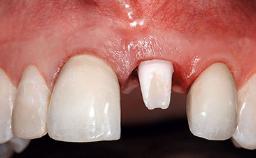

A 32-year-old female Caucasian patient with a compromised maxillary right central incisor was referred to us by a general dentist. Her chief complaints were discomfort and mobility of tooth 11 with unsatisfactory esthetics due to discoloration. The patient reported a previous trauma, some years earlier, as the origin of pathology on the afflicted tooth. Anamnesis was negative for any other dental or periodontal pathology in the remaining dentition. The patient did not take any medication and reported to be a light smoker (5–10 cigs/day). She had high esthetic expectations of her treatment. The extraoral examination revealed a high smile line with full exposure of her maxillary teeth and surrounding soft tissue in the area between the second premolars.

Patient's Esthetic Expectations Low Medium High

Lip Line No exposure of papillae Exposure of papillae Full exposure of mucosa margin